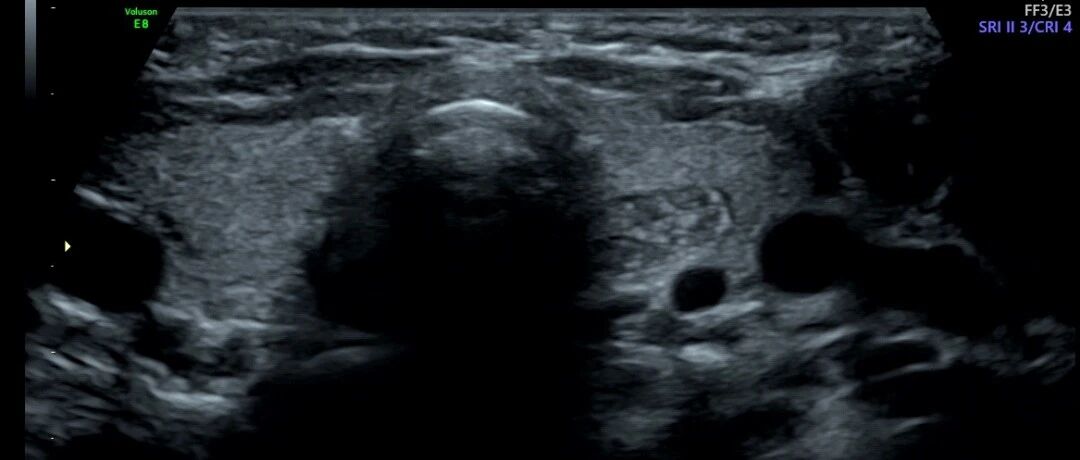

这个病例是子宫肌瘤还是内膜异位?其实都不是! 丁香园超声时间 · 公众号 · 医学 · 1 年前 · |